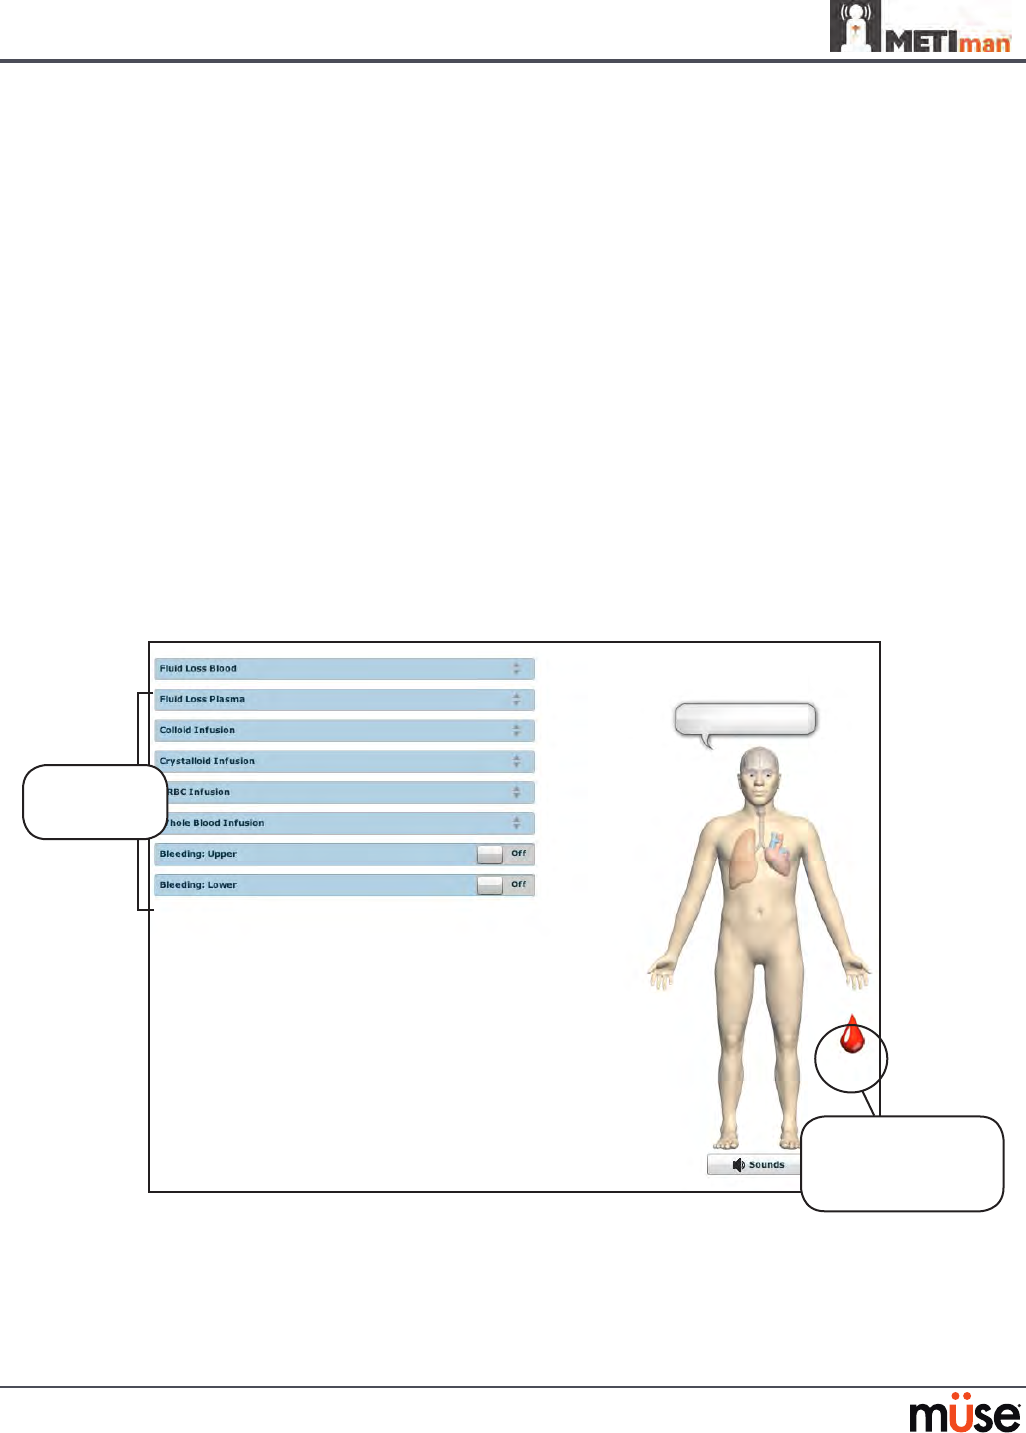

To enable bleeding, on the Run screen, click the blood droplet. The Fluids view appears.

The Fluids View

Click the blood

droplet to access

the Bleeding view

Bleeding

parameters

Fluid Loss Blood

To manually control a patient’s blood loss, from the Fluids view, click the Fluid Loss Blood

parameter. The Fluid Loss Blood slider appears. Set the amount of blood loss by dragging the

arrow up or down. Click Accept to exit and save the changes.

Fluid Loss Plasma

To manually control a patient’s plasma loss, from the Fluids view, click the Fluid Loss Plasma

parameter. The Fluid Loss Plasma slider appears. Set the amount of Plasma loss by dragging the

arrow up or down. Click Accept to exit and save the changes.